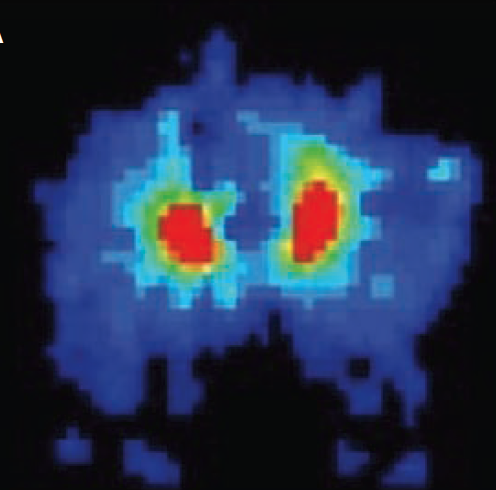

The patient had been in a wheelchair 12 hours a day for the past year and had difficulty pushing up from the chair for decompression. As part of the intervention, interface pressure was measured by the pressure mapping systems (range, 0 mm Hg–350 mm Hg). The values were as high as 319 gf/cm2 at the left ischial region and 325 gf/cm2 at the right ischial region with the patient using an air cell-based high-profile cushion while seated in a wheelchair (Figure 2A). The authors of the current report advised the patient on cushion selection and decompression movements. Based on the results of the interface pressure measurement, the patient was instructed to achieve decompression by leaning forward for a period of several seconds every 15 minutes (Figure 2B). The detection of DTI by MRI may have led to early intervention and healing in this patient, who was discharged 3 months later without progression to a deep pressure ulcer.